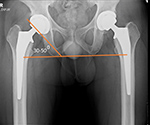

| Bilateral total hip arthroplasty (THA) |

| 38 year old man with bilateral THA for advanced osteoarthritis. The acetabular cup on an AP view of the pelvis should have 30-50 degrees of lateral inclination, which is measured as the angle between the rim of the acetabular cup and a line tangential to the ischial tuberosities. |

38 year old man with bilateral THA for advanced osteoarthritis. The distances from a line (C) between the centers of the femoral heads to a line running tangential to the ischial tuberosities (A) should be equal on each side, and the distances between the centers of the femoral heads to a line (B) running tangential to the tops of the greater trochanters should be equal on each side. Lines A, B, C should be parallel. |

38 year old man with bilateral THA for advanced osteoarthritis. The distances from the centers of the femoral heads on each side to the tops of the acetabular tear drops should be equal. |